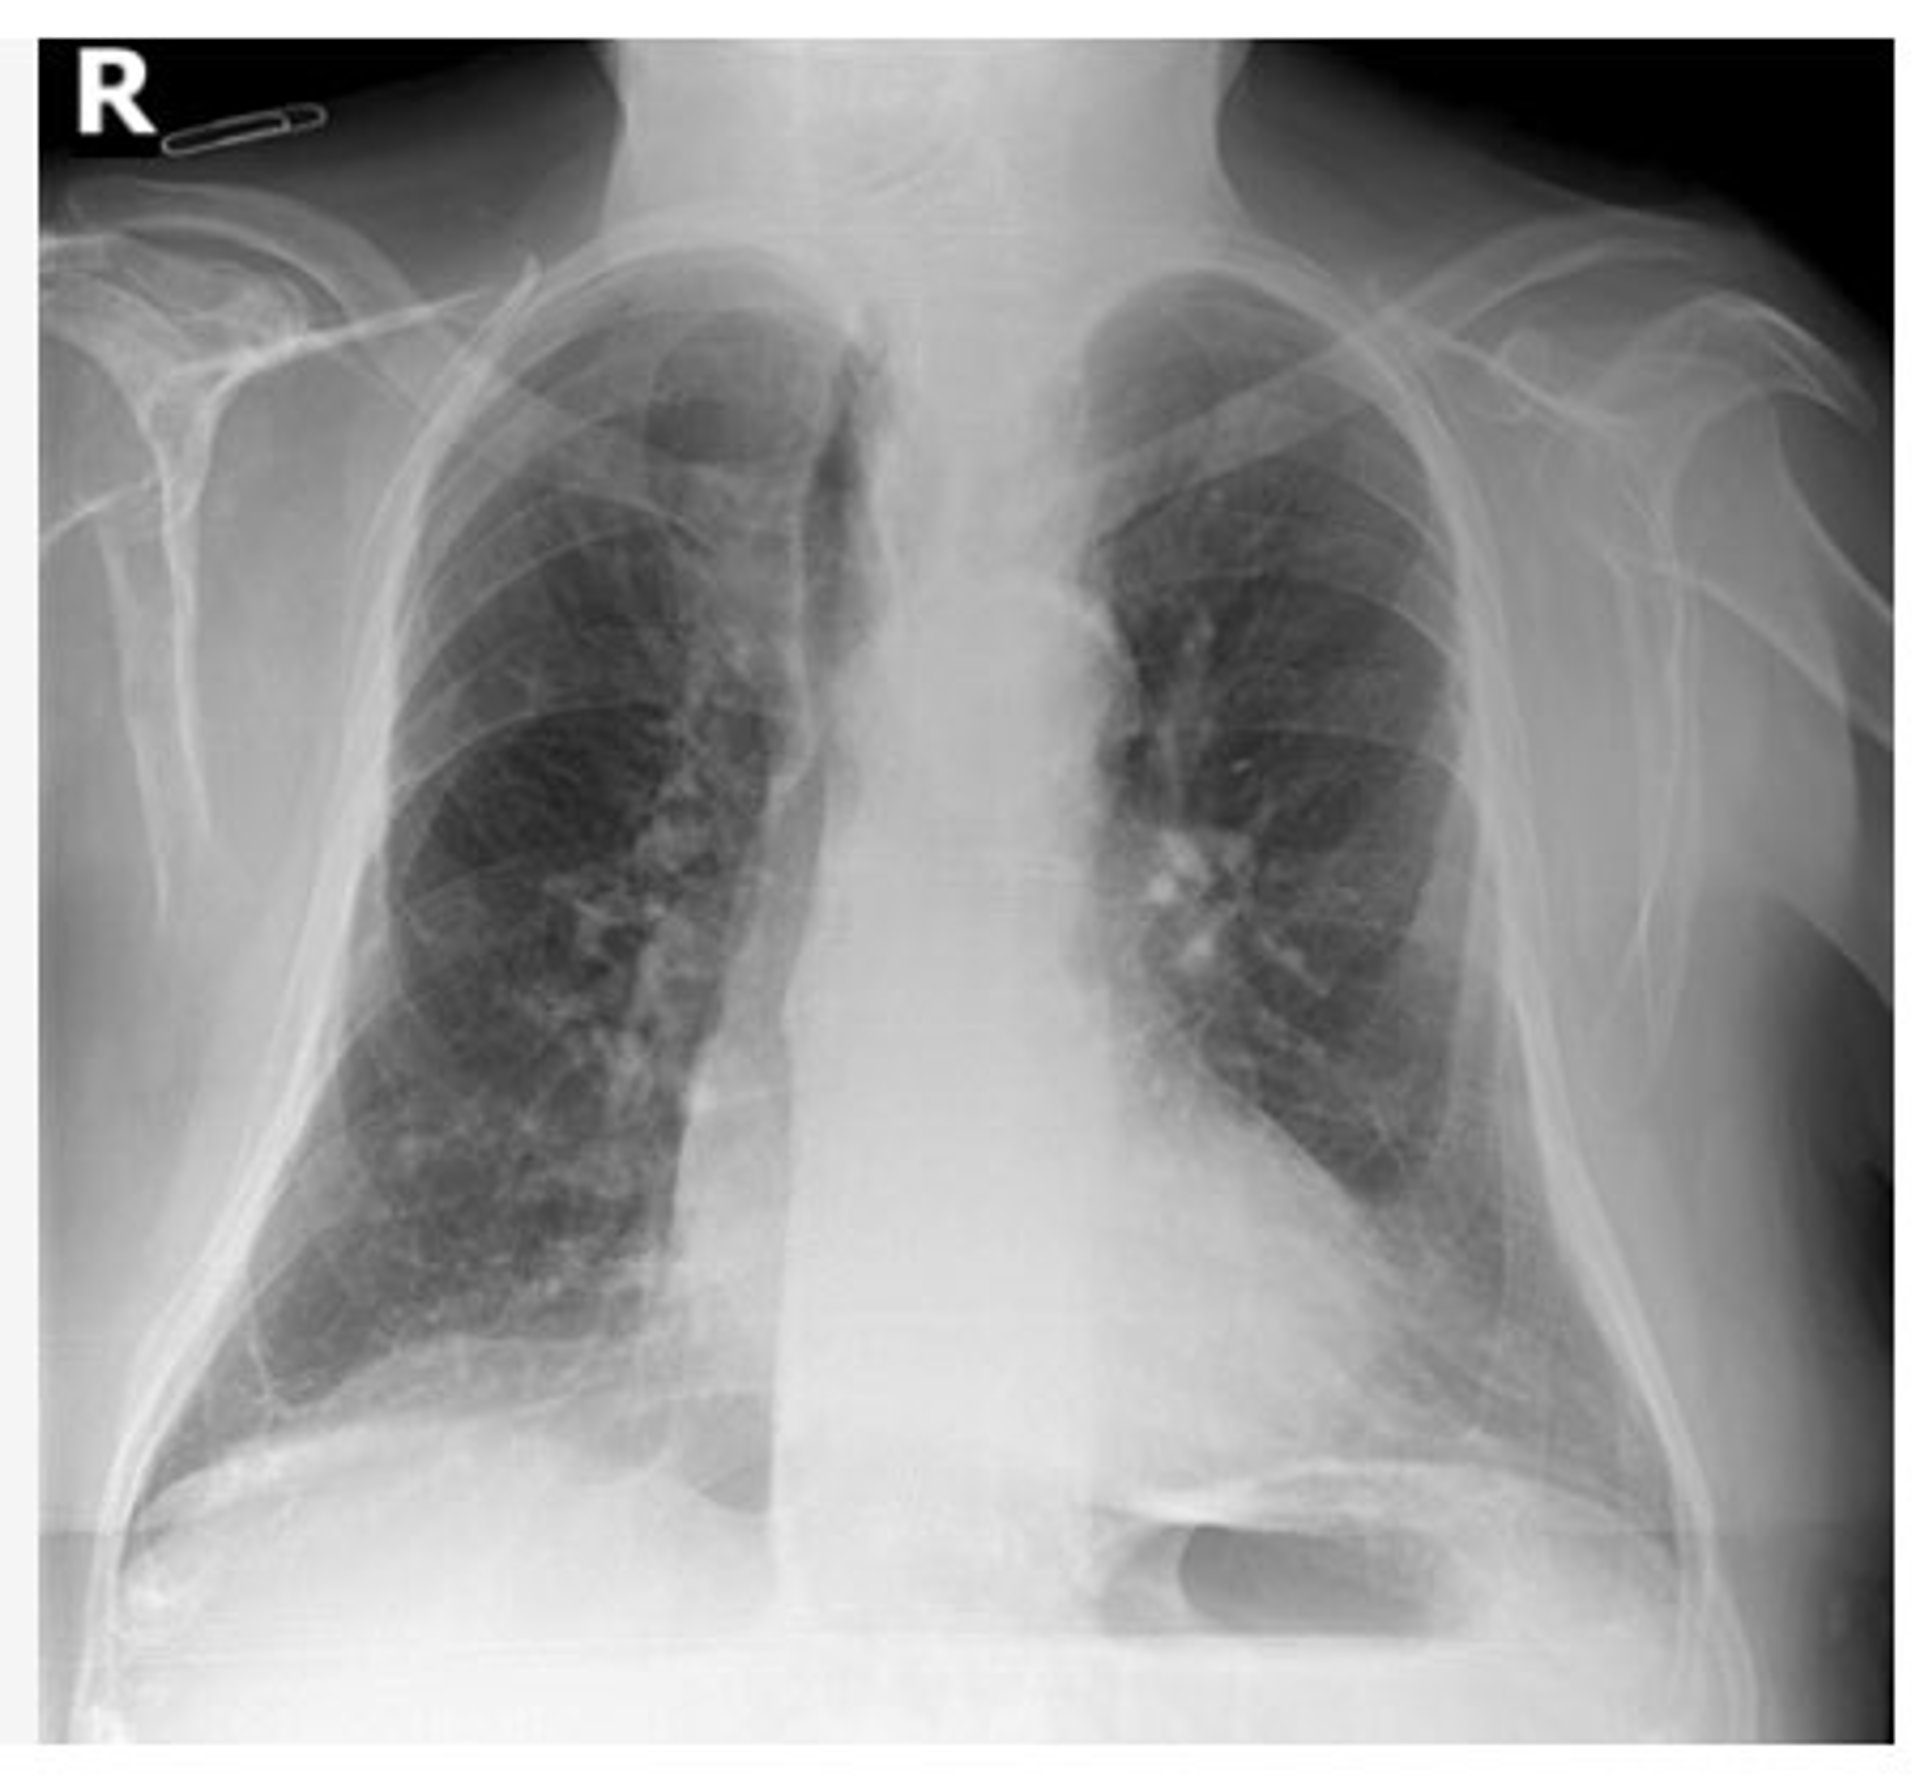

Radiografía de tórax

Radiografía de tórax - GVA